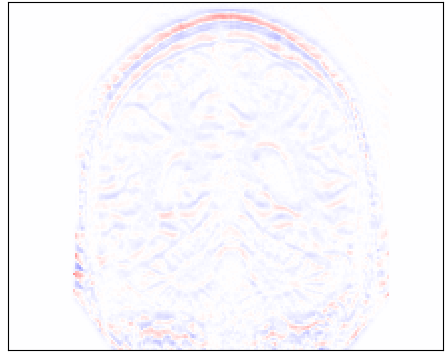

Refer to caption

(a)

(b)

(c)

Figure 4: Qualitative evaluation of reconstruction performance of our method on cardiac cine MRI (ACDC dataset). (a) Original cardiac MRI scan; (b) Its reconstruction and (c) Differences between original (minuend) and corresponding reconstructed (subtrahend) slice. Note that to reconstruct a slice xnsubscript𝑥𝑛x_{n} the mixing coefficient α𝛼\alpha in Equation 1 is set to zero. Blue corresponds to negative and red to positive differences. Image intensities are scaled to a [0,1]01[0,1] range. All difference images use the same color scale [1,1]11[-1,1].